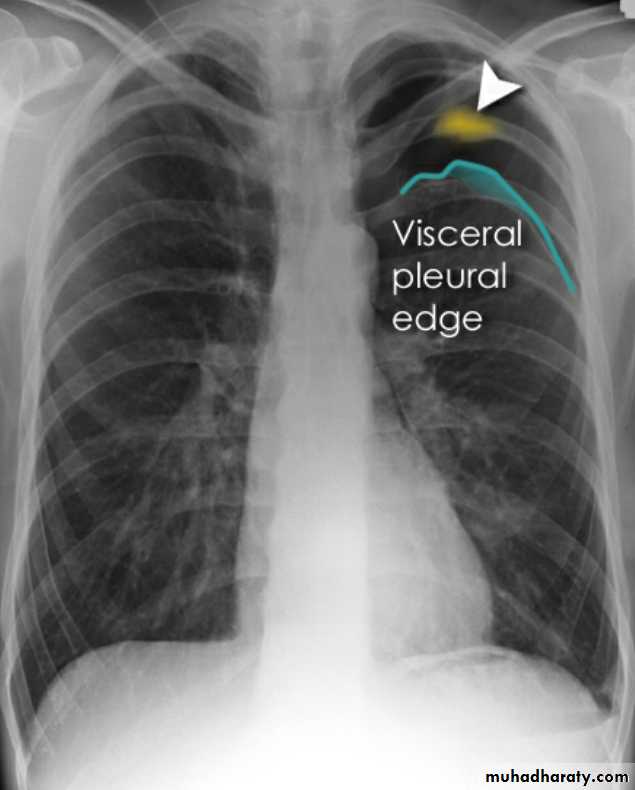

pneumothorax

53.pnuemothorax

54. pneumothorax

55. pneumothorax Right sided aspect